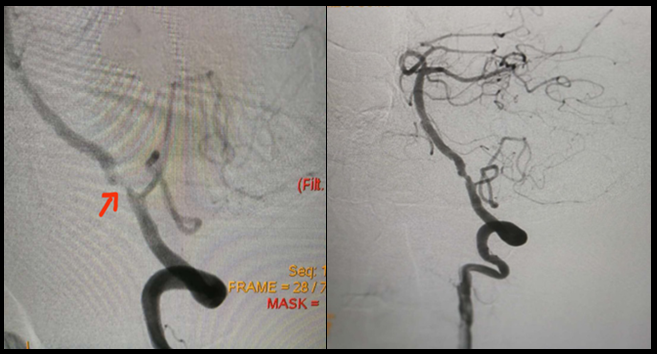

左图:TCD下多见血管狭窄处的血流速度加快和频谱异常;

右图:颈动脉超声所见的血管管腔狭窄和实际血流情况